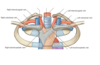

Label the image of coronary sulcus

What sulci separates the 2 ventricles + what does it contain?

- Anterior and posterior interventricular sulci

- The anterior interventricular sulcus is on anterior surface of the heart -> contains the anterior interventricular artery and great cardiac vein

- Posterior interventricular sulcus is on diaphragmatic surface of heart -> contains posterior interventricular artery + middle cardiac vein